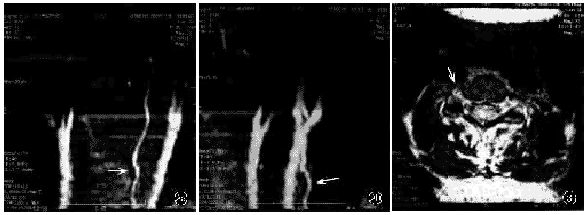

男,53岁,高处坠落致头颈部损伤,四肢活动障碍2 d入院。查体:患者神志清楚,四肢不全瘫。X线片示:C5椎体前上缘骨折,C4,5半脱位(图1),MRI示:C4,5椎间盘稍膨出,脊髓在C4,5椎体平面有挫伤变性。MRA扫描发现右侧椎动脉完全无血流成像,C5水平常规MRI T2横断面上,右侧椎动脉内可见到高信号血栓影像(图2~3),确诊为右侧椎动脉损伤。

多数学者认为,在非穿通性颈椎创伤中,椎动脉损伤主要是由于牵伸所致[1,8]。椎动脉第二段被固定在横突孔内,颈椎骨折脱位时,椎动脉在邻近两个横突孔间受到过度的牵伸而张力增大,造成血管内壁原发性挫伤,继之腔壁血栓形成,血凝块不断扩大,最终形成完全性栓塞。在常规MRIT2横断面上,椎动脉内可见到高信号的血栓影像,这也是区别于椎动脉先天性缺如的依据(图3)。此外,少数情况下,短暂的血管痉挛也可造成椎动脉阻塞。

图2MRA正、斜位椎动脉影像 a MRA示左侧椎动脉成像清楚(箭头示),右侧椎动脉完全无成像(C2~C6段) b 斜位MRA示左侧椎动脉成像清楚(箭头示),右侧椎动脉完全无成像(C2~C6段) 图3 C5水平MRIT2横断面上,右侧横突孔处椎动脉内可见高信号血栓影像(箭头示)